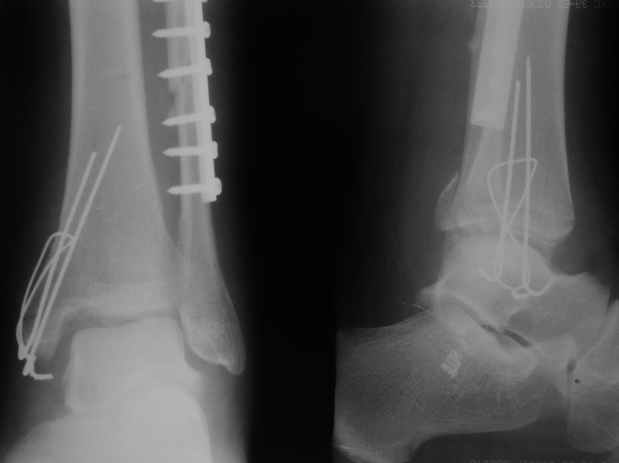

Мы бы, сблизив берцовые кости чрескожно наложенным репозиционным зажимом, провели позиционный межберцовый винт чуть ниже пластинки в положениий максимального тального сгибания стопы и ... на следующий день разрешили бы полностью наступать без гипса, брейса и т.п., но в обуви с небольшим каблуком 2-3 см и супинатором. Через месяц-полтора -винт удалить (если конечно не сломается).

Выполнено действительно неплохо, только позиционный винт забыли провести.

Вот и я тоже так думаю.

Перелом типа Вебер С с эверсионным механизмом травмы всегда сопровождается повреждением дистального межберцового синдезмоза, поэтому вместе с фиксацией переломов лодыжек( малоберцовой кости) автоматом выполняется фиксация синдесмоза винтом, который обычно удаляется через 8 недель -

перед началом полной нагрузки на ногу.

С мнением «провести позиционный межберцовый винт чуть ниже пластинки в положениий тыльного сгибания стопы» согласен, но я бы нагрузку начал через три недели и удаление шурупа можно провести через 6-8 недель.

Здесь похожий случай трехнедельной давности, перелом почти сросся и была укорочена малоберцовая, на операции длину малоберцовой смогли восстановить только после того, когда проксимальнее пластины ввели шуруп и использовали его как толкатель, с помощбю дистракционого инструмента (lamina spreader).

Меньше всего волнует положение медиальной лодыжки - в любое время можно провести остео или реостеосинтез, при несращении можно просто резецировать без ущерба для движений в голеностопе. Здесь обошлись фиксацией одним 4 мм канюлированным шурупом.